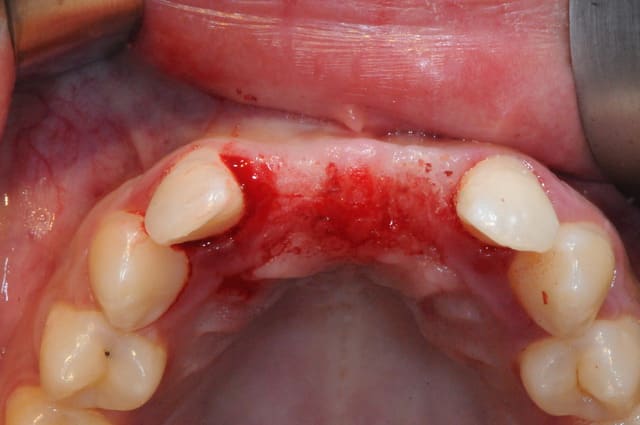

juste pour le plaisir des yeux...

j'étais hier à Strasbourg dans une formation avec Fouad Khoury.

génial ce type!